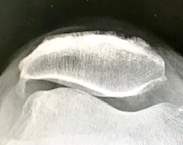

The Knee Also Rises

“The sunrise view” — that’s the formal name of the featured image in this post which is an x-ray of my right knee flexed. It’s called the sunrise view because the patella (the kneecap) appears to be rising over the… Continue reading